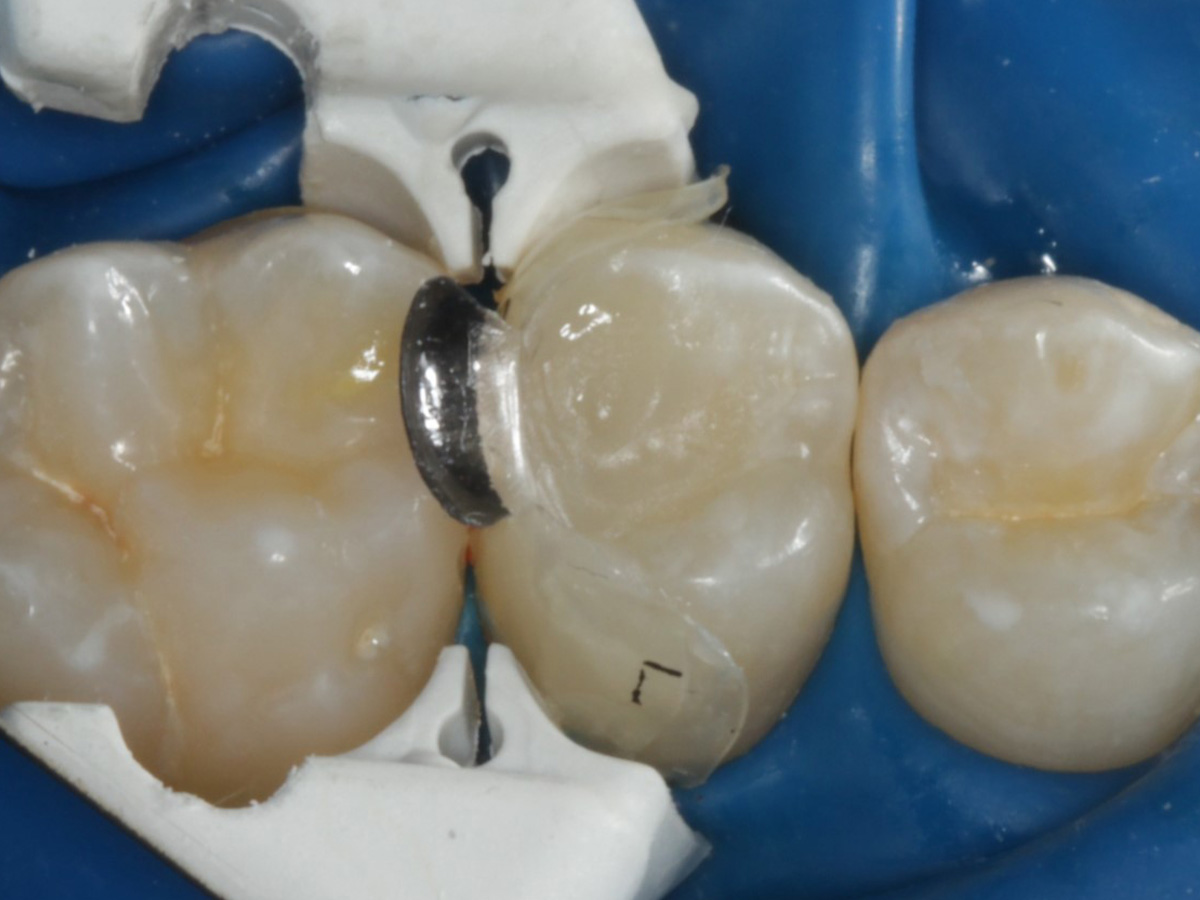

Abbildung 9

Nach Applikation der Matrize: Evolve Schwarz Prämolar- 7 mm; Schmelzätzung

Abbildung 10

Nach Spray und Trocknung der Kavität: perfekte Adaptation der Matrize insbesondere tief subgingival